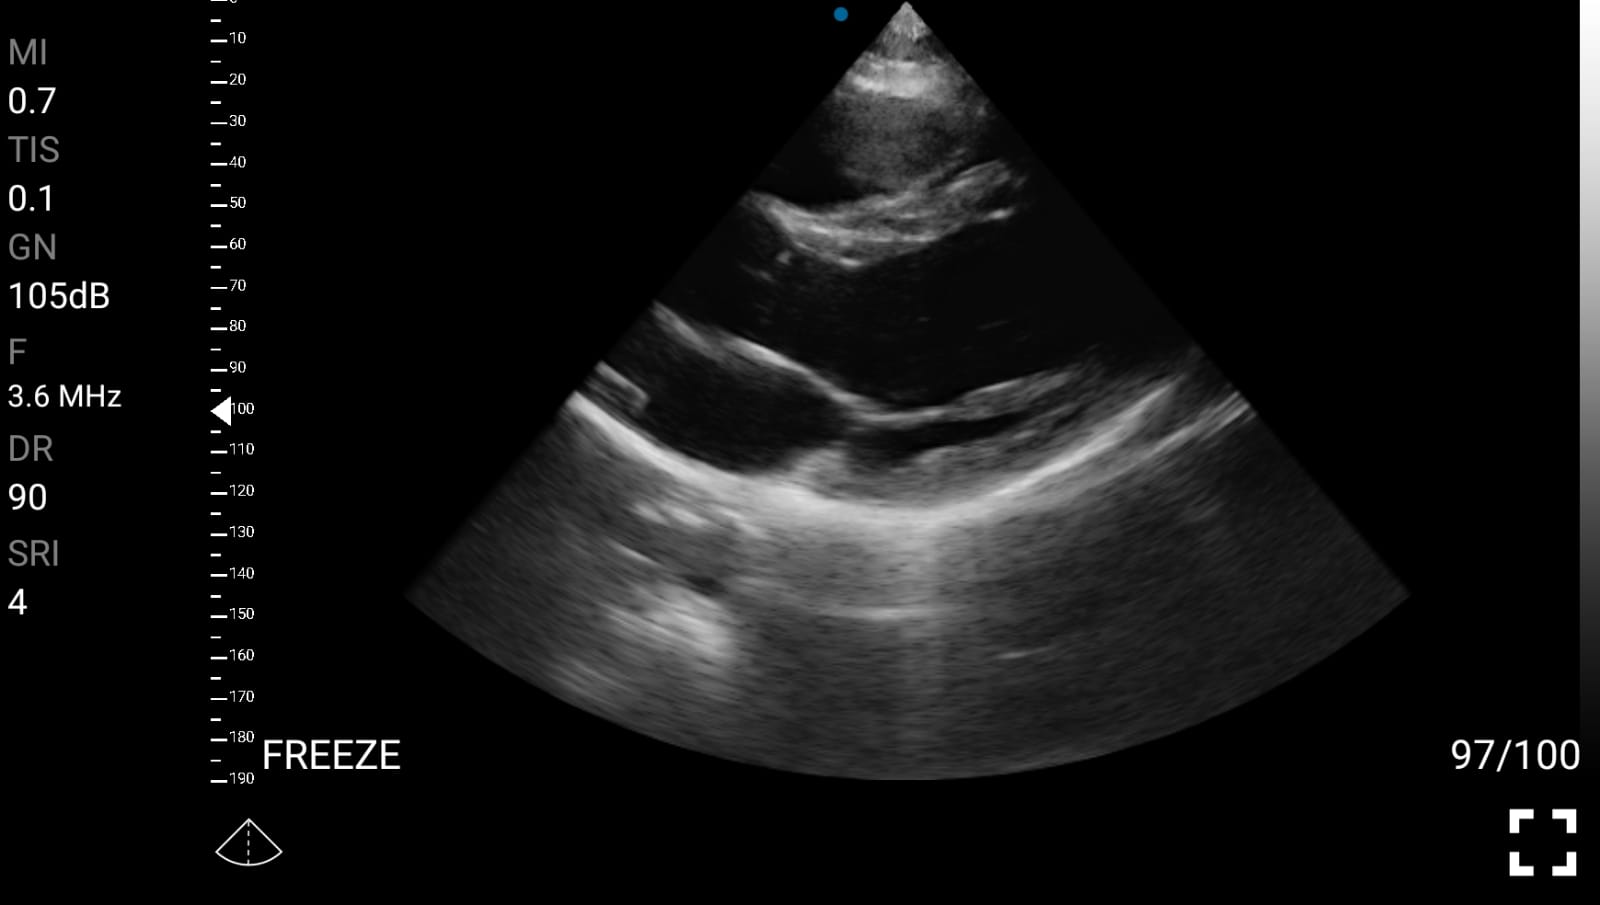

• Καρδιολογική Απεικόνιση για Κλινική Αξιολόγηση

• Εκτίμηση κλάσματος εξώθησης (EF): Προσέγγιση της συστολικής λειτουργίας της αριστερής κοιλίας.

Παραδείγματα

Ολες οι παραπάνω απεικονιστικές εξετάσεις έχουν ληφθεί από φορητή συσκευή όπως: Apple Iphone, Tablet, Samsung Mobile Phones και διάφορες άλλες φορητές συσκευές.

Παραδείγματα Video